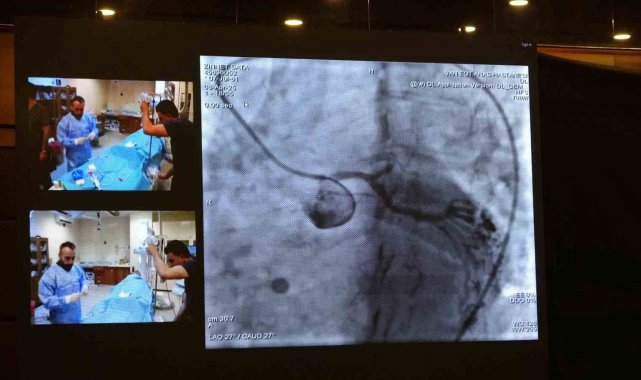

Türkiye'nin önemli kardiyoloji etkinliklerinden biri olan Girişimsel Kardiyovasküler Akademi 2025, bu yıl Van'da düzenlendi. Kardiyovasküler Akademi Derneği'nin öncülüğünde yapılan sempozyum, Van YYÜ ve Van Eğitim ve Araştırma Hastanesi Kardiyoloji Kliniği'nin ortak çabasıyla hayata geçirildi. Van Eğitim ve Araştırma Hastanesi'nin kateter laboratuvarlarında gerçekleştirilen 12 canlı vaka oturumunda; sol ana koroner müdahaleleri, bifurkasyon ve kompleks PFO/ASD vakaları, tam tıkalı damar (CTO) işlemleri, karotis, EVAR, TAVI, apendiks kapama, septal ablasyon ve mitral balon valvüloplasti gibi işlemler başarıyla uygulandı.

Hastanede gerçekleştirilen canlı vaka işlemlerinin Türkiye'deki tüm kardiyologlar tarafından izlenebildiğini belirten Van Eğitim ve Araştırma Hastanesi Başhekimi Doç. Dr. Remzi Sarıkaya ise "Bu bizim için son derece önemli bir adım. Gerçekleştirilen vakaların tamamı oldukça zorlu vakalar olup, geçmişte bu tür işlemler bu bölgede yapılmazken, son dönemde hem ilimizde ciddi bir şekilde yapılmaya başlanmış hem de tecrübe aktarımı noktasında önemli bir aşama kaydedilmiştir. Tüm ekip arkadaşlarımı bu başarılarından dolayı kutluyorum. Peki, bu canlı vakalar nelerdir? Ameliyatsız aort kapak değişimi, kalp deliklerinin kapatılması, daha önce tek seçenek olarak ameliyatla tedavi edilen ciddi ana koroner lezyonları ve çatallanma olarak adlandırılan bifurkasyon stentlemeler, sol atriyal apendiks kapama dediğimiz pıhtı atan deliklerin kapatılması, aort damarda var olan anevrizmaların kapatılması gibi son derece zor ve karmaşık vakalar burada canlı yayında gerçekleştirilerek tecrübe aktarımına imkan sağlamaktadır. Bu tür bir toplantının ilimizde yapılması ve bu tecrübe aktarımının gerçekleştirilmesi bizim için büyük bir gurur kaynağıdır" diye konuştu.